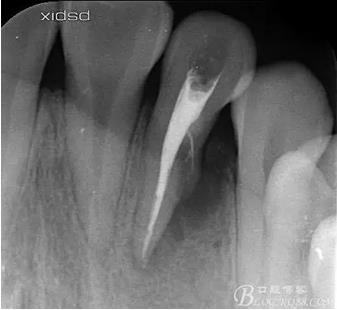

(1) 檢查:12唇側(cè)牙齦可見竇道,牙體顏色較鄰牙暗,無光澤,形態(tài)完整無缺損,唇側(cè)及近遠中向未提及牙周袋。腭側(cè)齦緣輕度紅腫,舌側(cè)窩可探及裂溝,可見浸墨狀痕跡,沿裂溝舌側(cè)探診牙周袋深大于11mm,除患牙外全口牙周狀況良好,為探及牙周袋,牙齦色粉紅。邊緣菲薄,質(zhì)地堅韌。12冷熱診無反應(yīng),叩診(+-),無明顯松動,無咬合創(chuàng)傷。12根尖x線片示,根管中三分之一中可見一斜向線樣透射影像根尖區(qū)及遠中根三分之一可見低密度透射暗影,錐形束CT示12根尖區(qū)唇腭向骨吸收已穿通,根面溝達根中三分之一卷曲分出另一牙根,再未見其他明顯的根管系統(tǒng)。